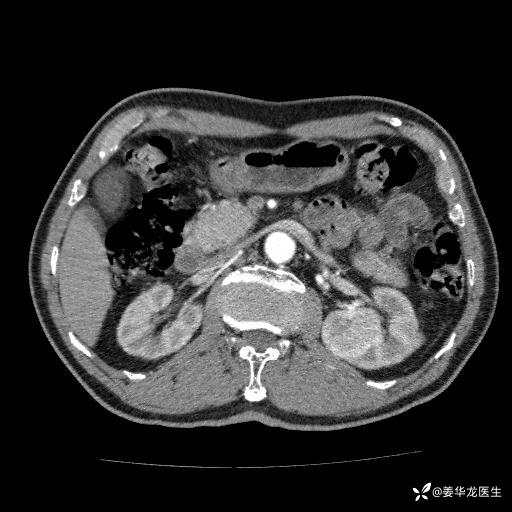

左肾中心型肾门部肿瘤39mm×34mm×36mm,右肾GFR25ml/min,部分切还是全切?

患者75岁老年男性,体重50kg,无高血压、肾病、糖尿病等基础病,检查发现左肾中心型肾门部肿瘤,右肾GFR只有25ml,无肉眼血尿,无镜下血尿。入院验血常规检查均正常,包括肾功能,肌酐102.7umol/L.

二、左肾肿瘤与左肾集合系、左肾动静脉关系密切,左肾部分切除术可行吗?成功率有多大?成功部分切后,肾功能还有多少?

三、患者无任何基础病,为什么右肾GFR只有25ml/min,反尔有肿瘤的左肾GFR达38.8ml/min?